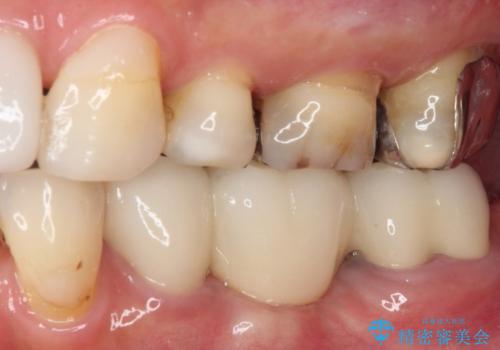

抜かずに保存した奥歯が痛くて臭う セラミックブリッジによる欠損補綴治療

- 以前抜歯を回避するために奥歯を分割して保存してもらったものの、痛みと異臭が気になるとのことで来院された患者様です。

診査したところ、保存は不可能と診断しました。

前後の歯も大きな銀歯が装着されていたので、抜歯後に治癒を待って、フルジルコニアブリッジにて補綴することとしました。

抜歯をしたことで、ずっと気になっていた異臭から解放されました。

前後の歯はいずれも神経が取り除かれている歯であったので、ブリッジ治療では負担が大きくなることが懸念されました。咬合力はさほど強くない咬み合わせであったので、インプラントではなく、ブリッジ治療を選択されました。